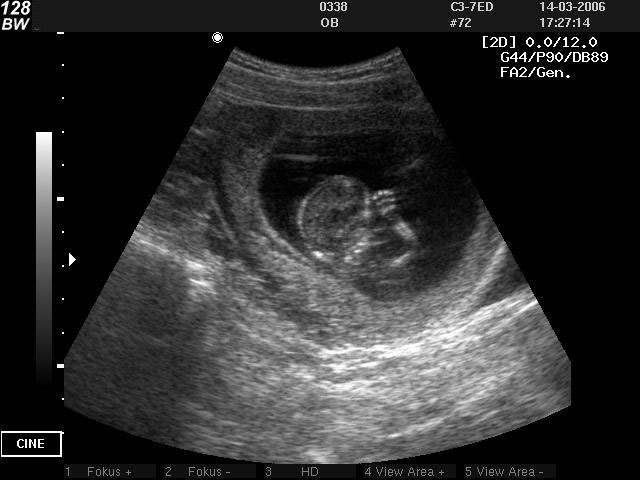

Фото УЗИ плода при беременности 8-9 недель . Во время УЗИ у эмбриона уже можно отчётливо различить отдельные сегменты - голову, туловище, конечности . Появляется первая двигательная активность .

Фото УЗИ ребенка на 15 неделе беременности . В этот период происходит активное развитие головного мозга и опорно-двигательного аппарата . Несмотря на то, что глаза малыша по-прежнему закрыты . . .

Фото плода УЗИ . Фотогаллерея "Детишки до рождения" . Галлерея "Детишки до рождения" доступна для просмотра в пределах 28-й недели беременности . Внешность вашего ребенка действительно . . .

На этой страничке вы можете разместить фото узи на 19 неделе беременности . Первые снимки крохи волнующи и умилительны, и будущий папа и родственники с удовольствием разделят с вами радость созерцания малыша в животике .

На фото УЗИ эмбриона сложно увидеть половые органы мальчика или девочки . Как врачам удается угадать пол малыша, и на каком сроке шанс точного определения пола максимально высок?